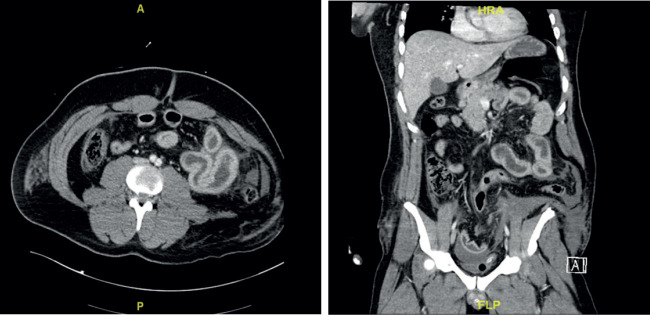

Case presentation: The patient presented to the emergency department after road traffic accident with a seat belt sign, Exploratory laparotomy unveiled extensive injuries, including complete jejunal transaction, avulsion of the terminal ileum, sigmoid mesentery avulsion, and rectosigmoid junction degloving with left anterolateral muscle destruction forming a traumatic hernia. Surgical interventions included jejunal resection and anastomosis, ileocecal limited resection and anastomosis, lastly Hartmann procedure and left high colostomy creation. Subsequent procedures addressed complications, in form of anastomotic leakage managed with resection of the ileocolic anastomosis and ileostomy creation, Vacuum-Assisted Closure dressing, and biological mesh placement to manage abdominal wall infection and dehiscence. After one year the patient underwent surgery for ileostomy and colostomy reversal, along with abdominal wall reconstruction using biosynthetic mesh.

Conclusion: Managing injuries involving the jejunum, ileum, and rectosigmoid requires careful surgical intervention, considering individual cases and surgeon judgment. Our experience highlights the need for a modification in the emergency room policies, advocating immediate computed tomography scans for patients with seat belt signs for early detection and improved outcomes.